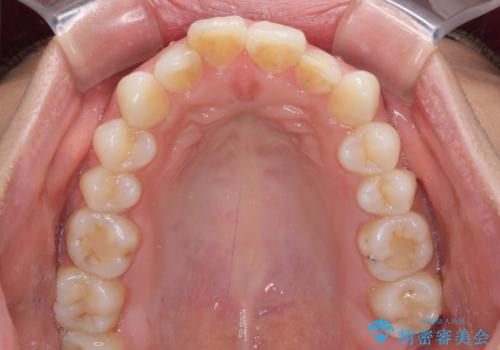

- くちばしのような前歯の突出感を気にして来院された患者様です。

上下左右第一小臼歯4本を抜歯して、積極的に口元を引っ込めるよう、ワイヤー装置にて矯正治療を行うこととしました。

抜歯矯正を行ったことで、顎先のつっぱり感や口元の閉じにくさを解消することができました。